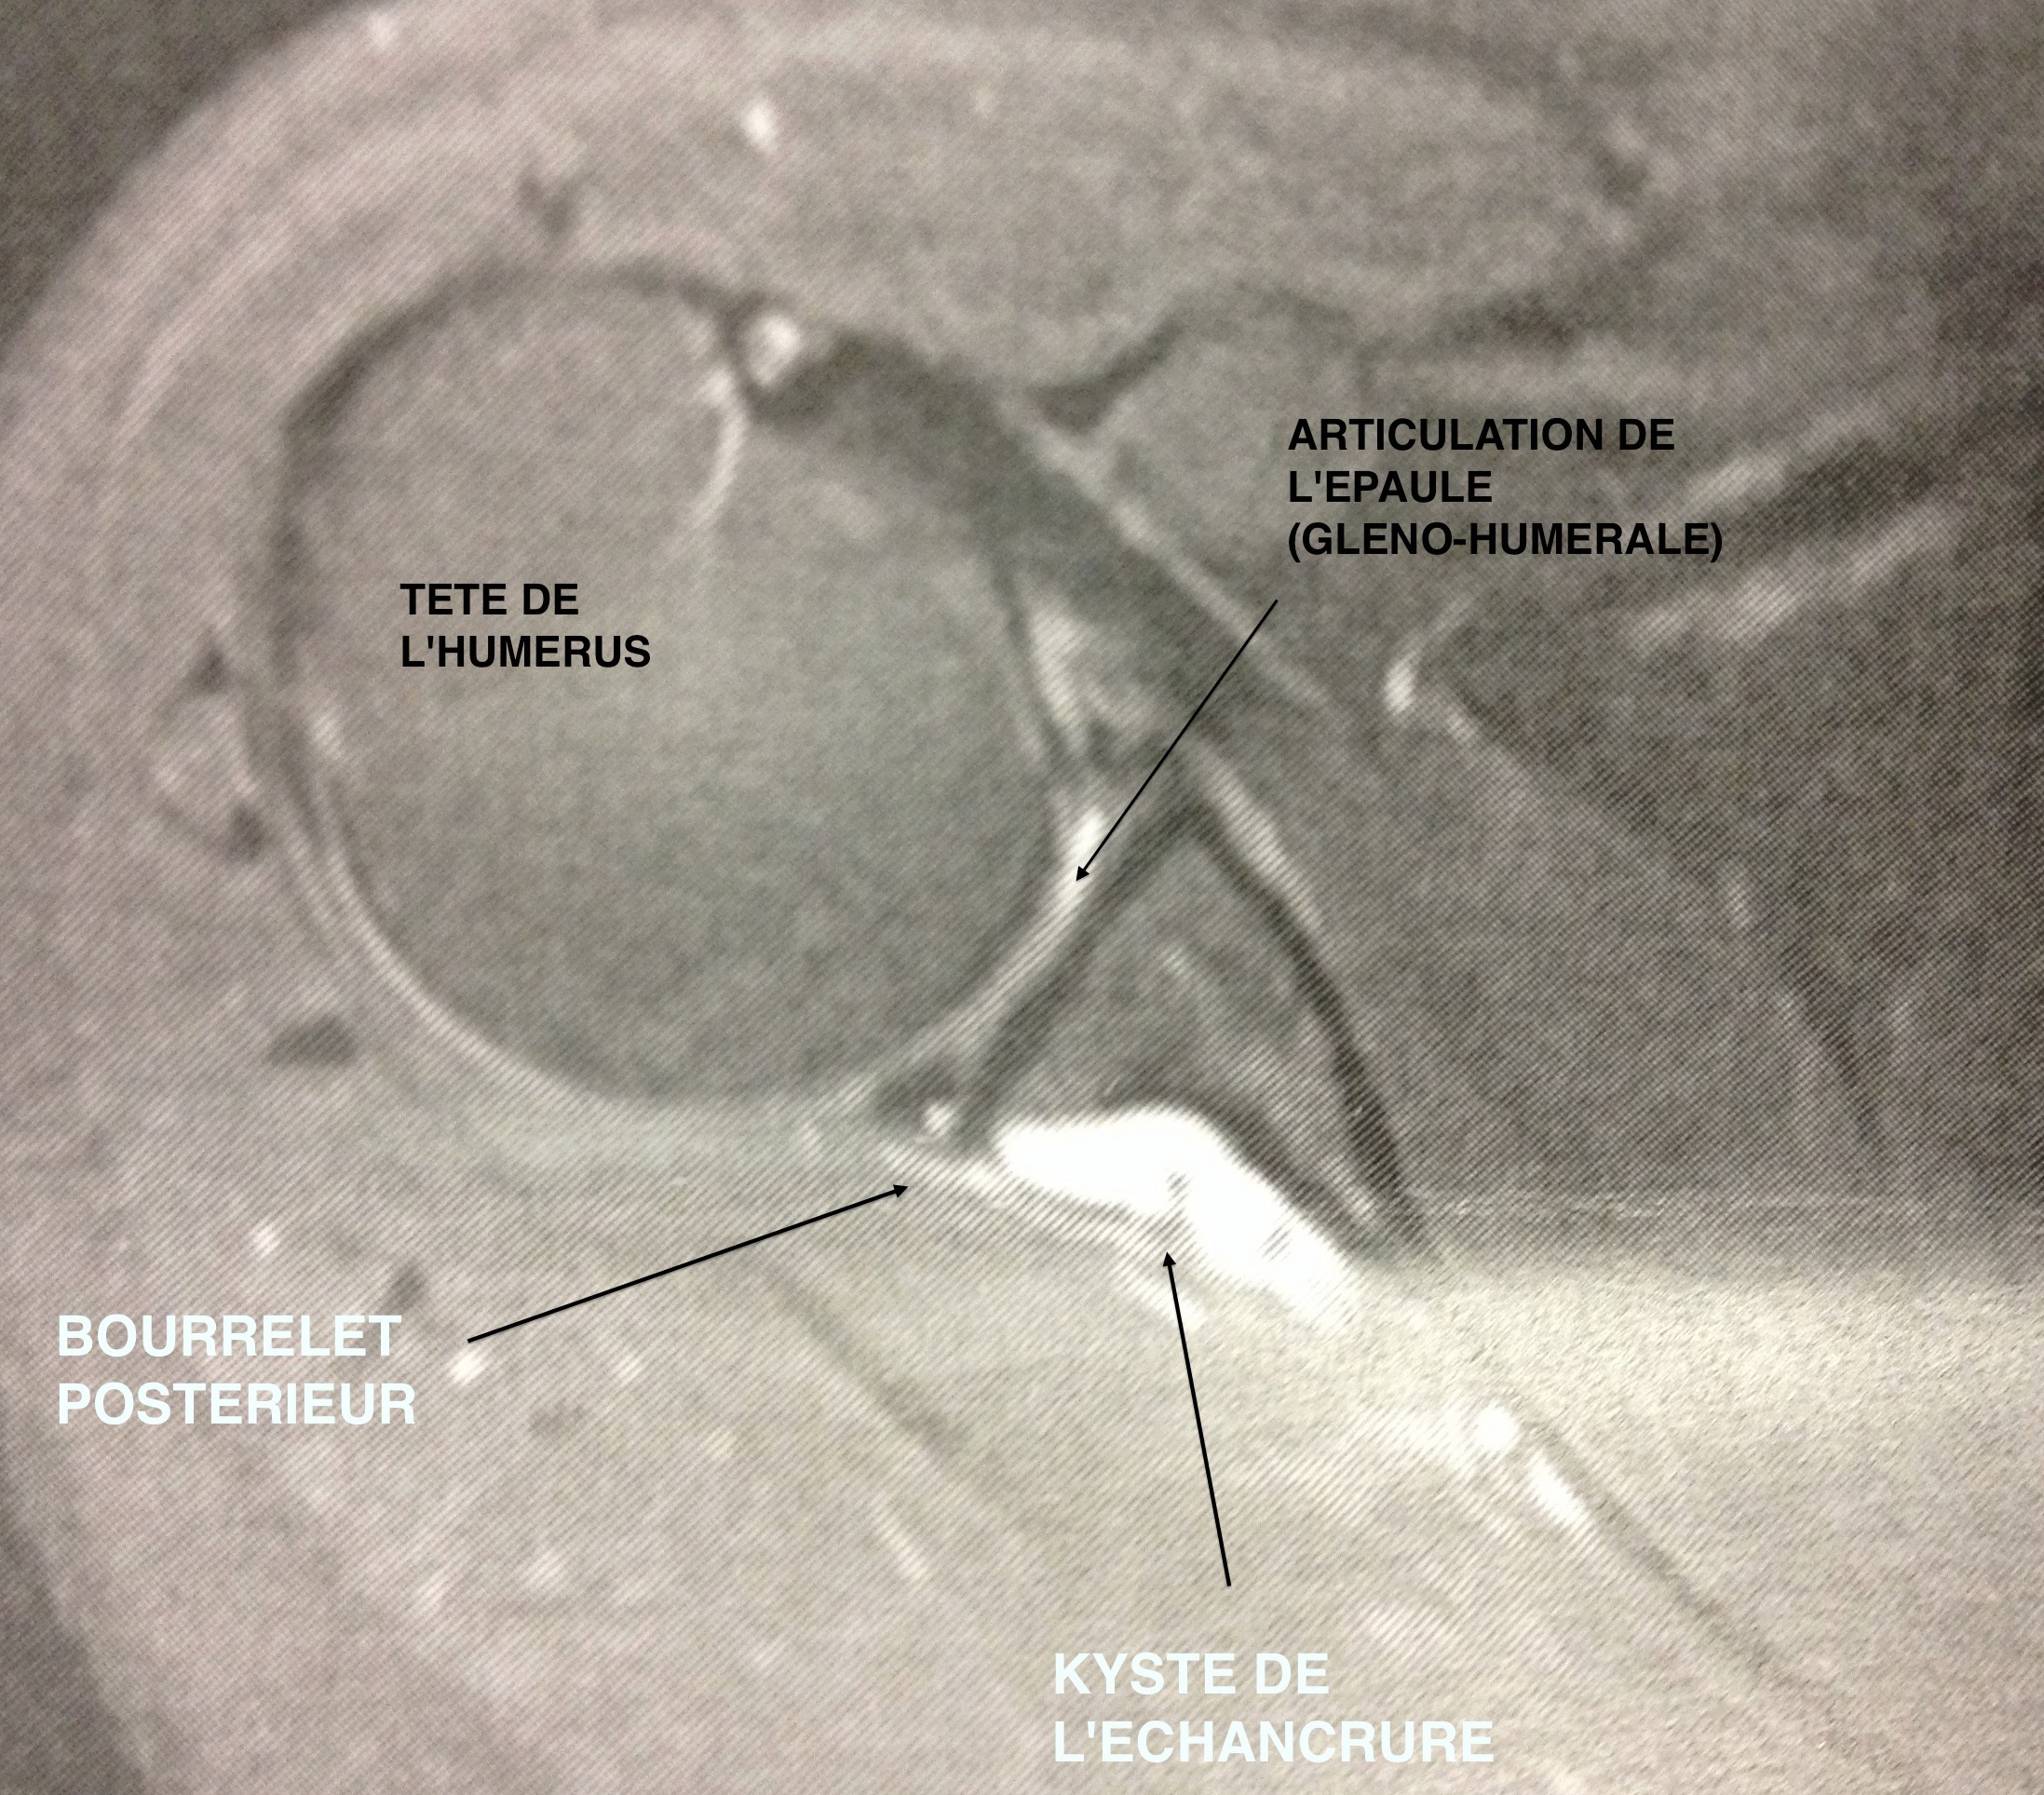

Dans le cas de compression au niveau de l'échancrure spino-glénoïde, la compression est très souvent associée à un kyste

issue d'une fissuration dans le bourrelet . Ce kyste est formé de liquide synovial communiquant avec l'articulation.

Figure 5 : Vue de haut (sagitale) de l'épaule par IRM montrant la présence d'un kyste

Figure 6 : Vue frontale de l'épaule par IRM montrant la présence d'un kyste